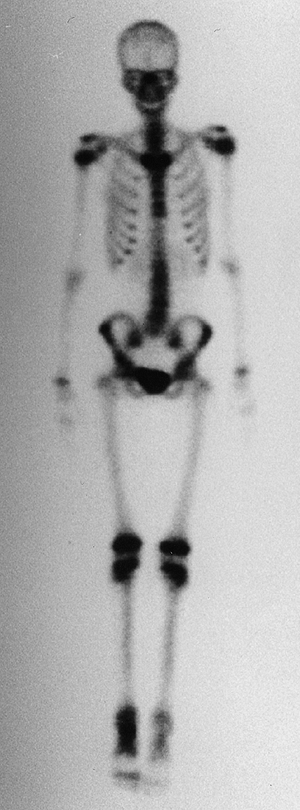

![]() |

Figure 14.2

An anterior view of a whole body technetium-99 bone scan. This patient has an osteoid osteoma of her talus, and there is increased activity in the talus. There is also increased activity in the distal tibia, which is thought to be a reaction to the local increased blood flow. Technetium-99 bone scanning is an efficient means of evaluating the entire skeleton of a patient with a bone lesion. It is important to have the entire skeleton scanned, rather than limit the scan to a small part of the skeleton. |